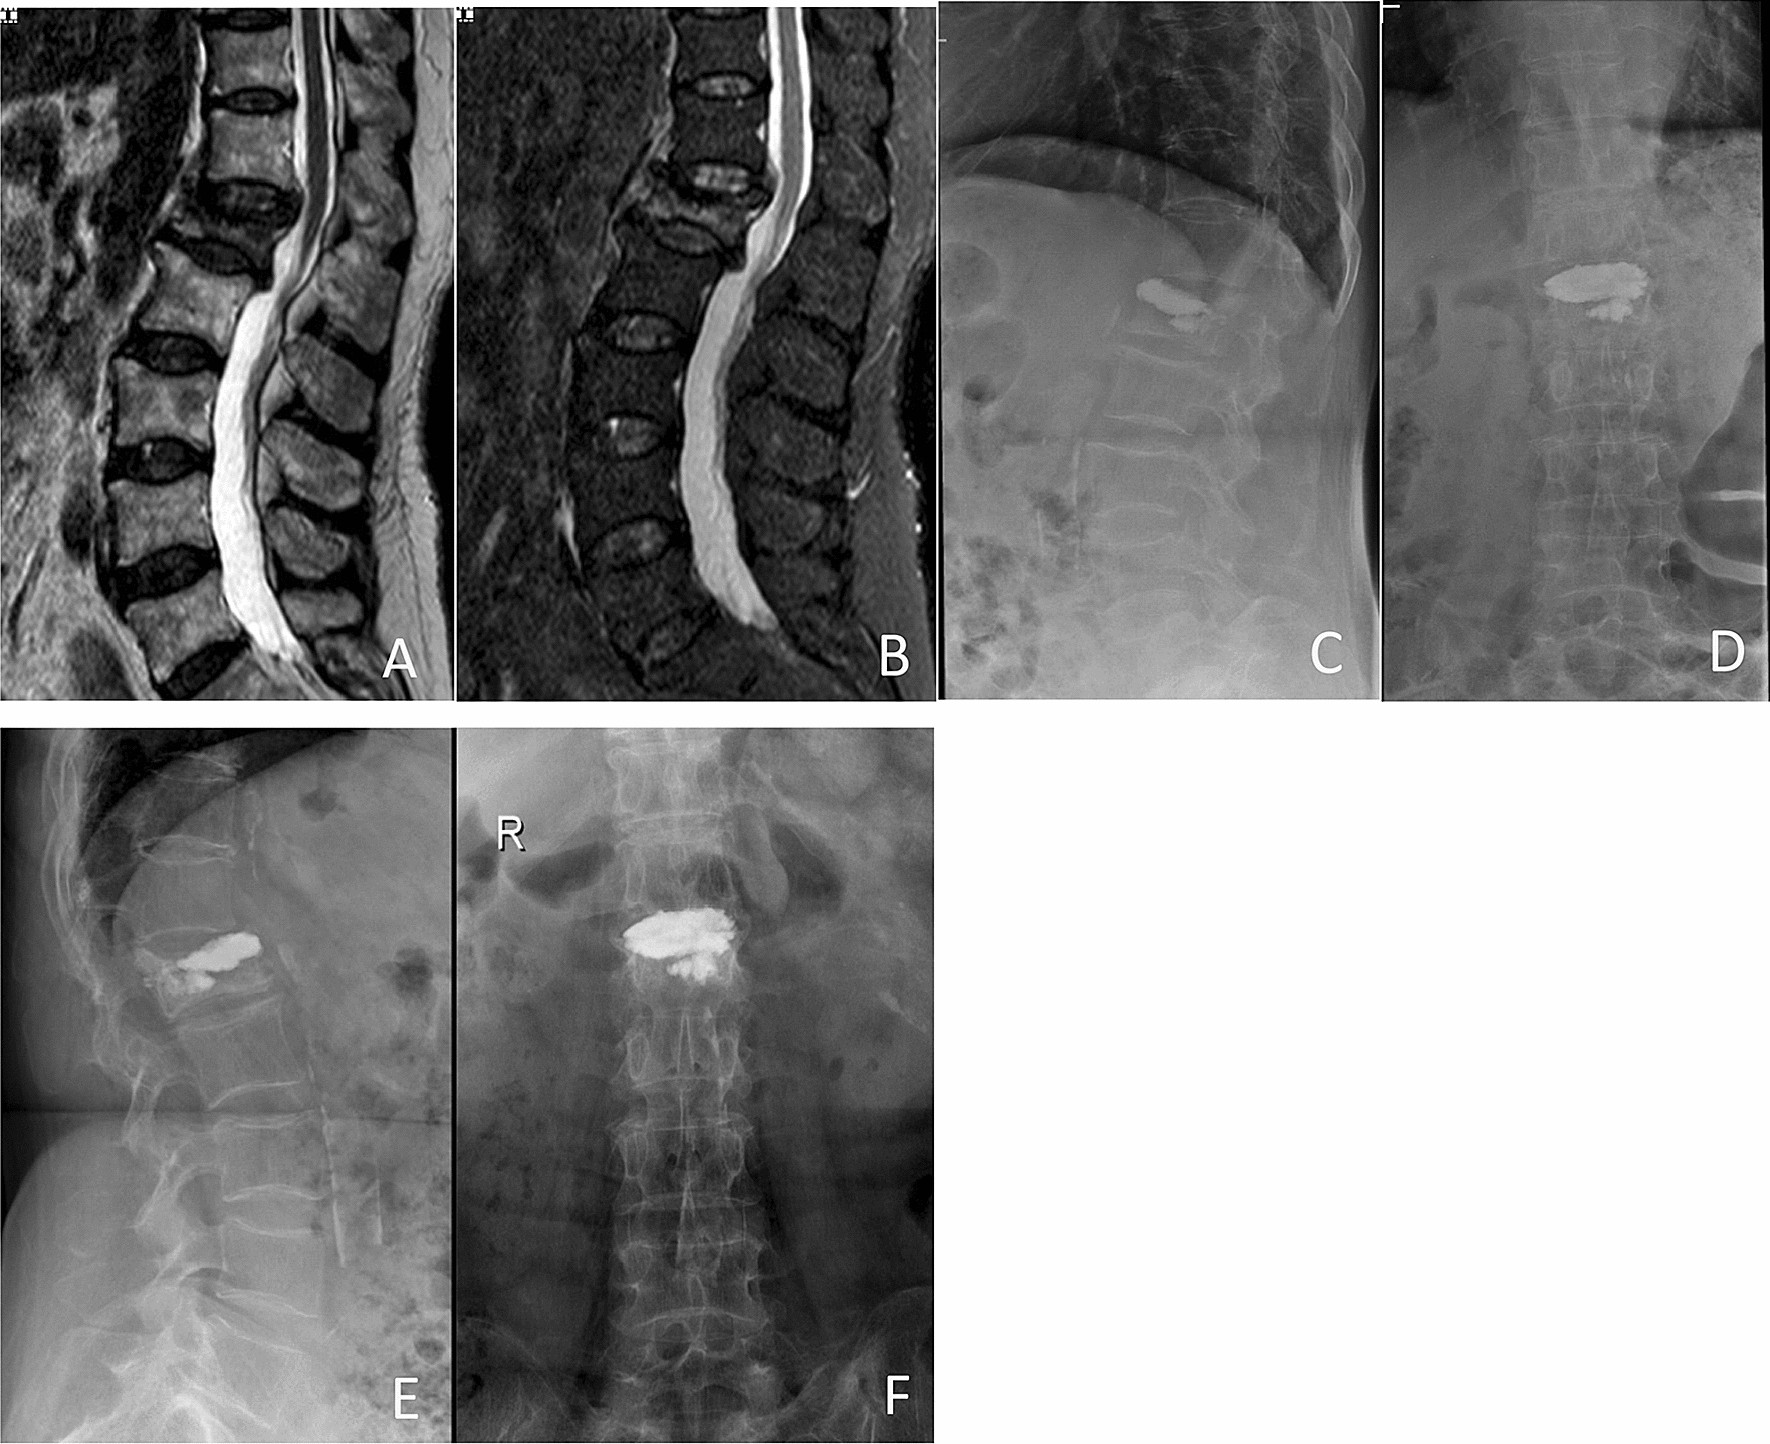

Figure 2

Preoperative and postoperative films of a 60-year-old woman with OVCFs of L1 vertebral body, treated with low-viscosity cement PKP. Preoperative MR image showing the compression fracture at the L1 level (A), (B). Anterior–posterior and lateral film showing the leakage of bone cement into the upper disc space postoperatively (C), (D) and at 1 year postoperatively (E), (F).